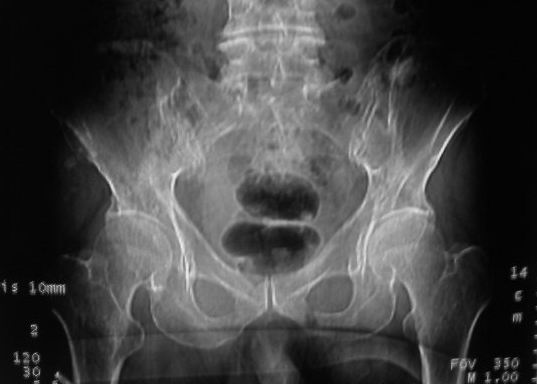

以下是引用zjzjr在2008-10-3 12:59:00的发言:[br]前列腺癌伴左髂骨\\腰椎转移可能性大.

以下是引用卜一在2008-10-3 13:40:00的发言:[br]前列腺癌!左髂骨\\腰椎转移?建议行全身骨扫描!

以下是引用深泽交通医院在2008-10-3 15:33:00的发言:[br]前列腺实性增大伴分叶状,与包膜间隙境界不清;椎体松质区间结节样密度影,考虑:前列腺癌,并椎体成骨性转移